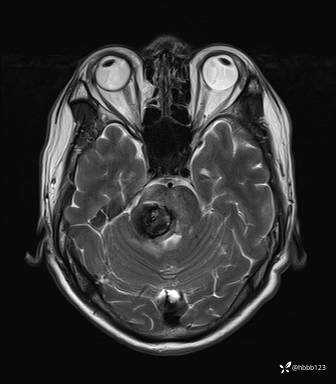

患者男,51岁。

简要病史:患者自述于1周前至某人民医院发现脑干肿瘤(具体不详),为求进一步诊断至我院就诊。

完善颅脑MRI平扫+增强,颅脑CT平扫:

T2: